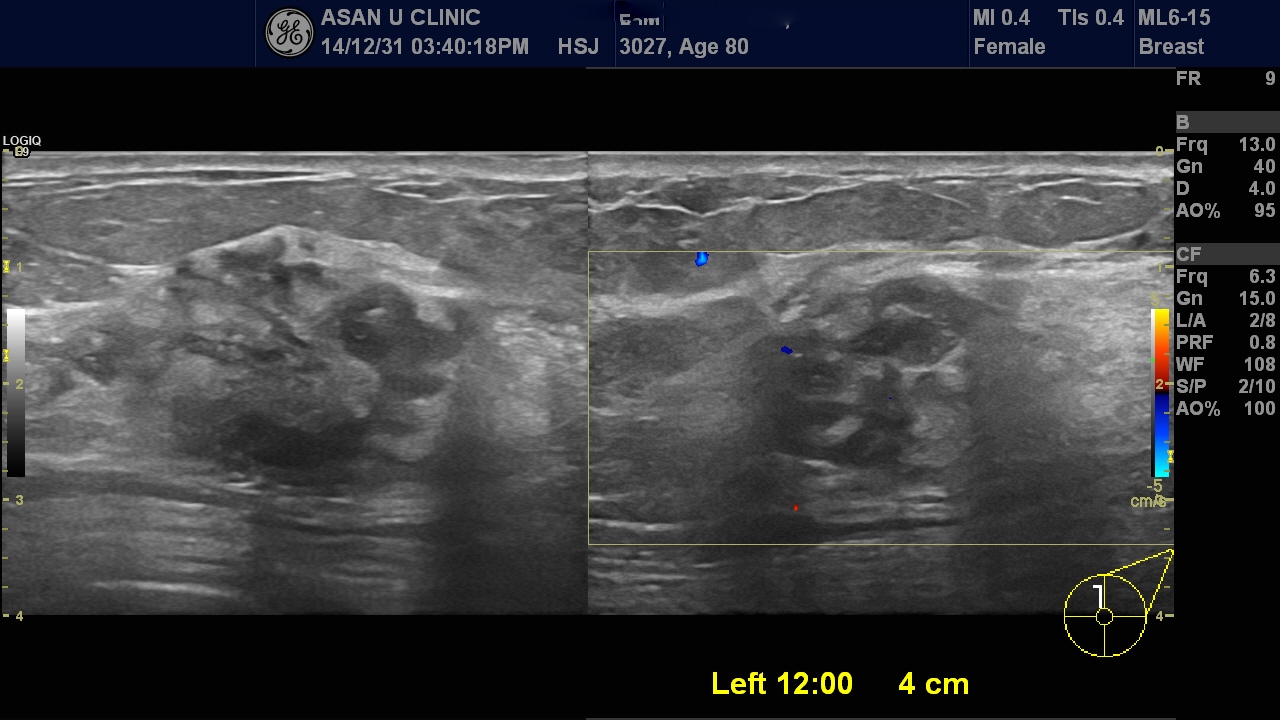

왼쪽 유방에 만져지는 몽오리로 내원하신 80세 여성분입니다.

초음파상 만져지는 부위의 혹 뿐아니라 왼쪽 겨드랑이에도 전이 의심 림프절 비대가 있어

함께 조직검사 시행하여 침윤성 유관암의 겨드랑이 림프절 전이로 진단되었습니다.